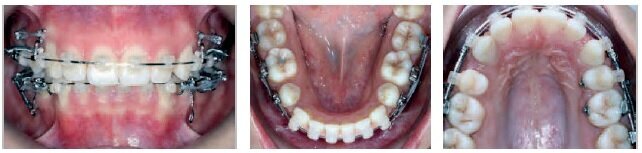

VISIT NO 1

Both appliances bonded on the same day.

SAP bracket placement

Torque Selection

Maxilla: Super low torque on the incisors – super torque on the canines.

Mandible: Low torque on the incisors – super torque on the canines.

014 CN archwires were placed along both arches, from the 1st molar to the 1st molar, without stops.

Bite turbos were bonded to 13 – 23 in order to unlock the occlusion, promote leveling, and protect the brackets on the lower arch.

VISIT NO 2: 4 MONTHS

The patient returned 4 months later. The arches showed excellent initial progress in terms of leveling.

New 014 archwires were placed to continue the leveling-alignment process.

Anterior stops were placed on both arches.